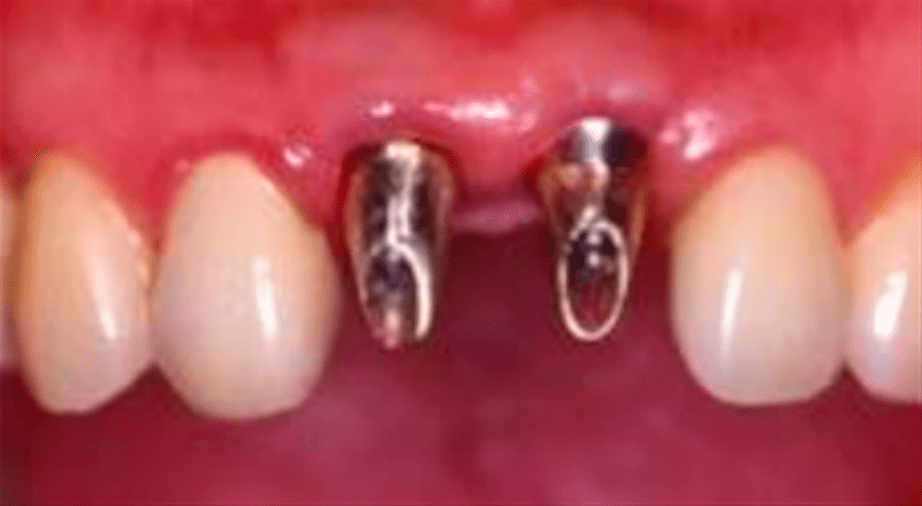

(图 / 患者植入植体 本图版权为祯诺ZENOIS,由好牙医提供)

(图 / 患者种牙效果 本图版权为祯诺ZENOIS,由好牙医提供)